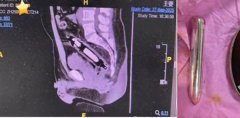

异物 支架 纤维 2025/03/08